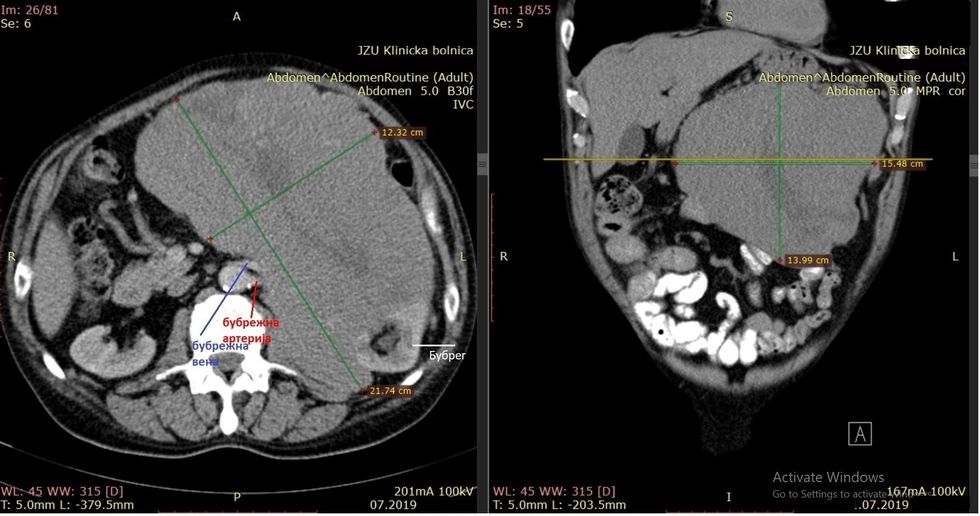

"Është konstatuar se pacienti i moshës 71 vjeçare, ka neurofibrosarkoma në anën e majtë në retroperitoneum. Pas ekzaminimeve në klinikë, u konfirmua se ka tumor të madh në bark. Gjithashtu ishin të qarta plagët nga biopsia e mëparshme. Ekzaminimi i MSCT tregoi se tumori kishte infiltruar veshkën e majtë dhe enët e saj të gjakut, si dhe në të njëjtën kohë ka infiltruar pankreasin. Për shkak të anemisë dhe kequshqyerjes, përgatitjet për operacion janë bërë sipas protokollit ERAS (Enhanced Recovery After Surgery)", tha kirurgu abdominal Millço Panovski, subspecialist në Klinikën "Zhan Mitrev".

Ekipi i kombinuar i onkologjisë, e përfundoi operacionin me sukses. Tumori i cili ishte me përmasa 27x17x14 cm, së bashku me omentumin është larguar.